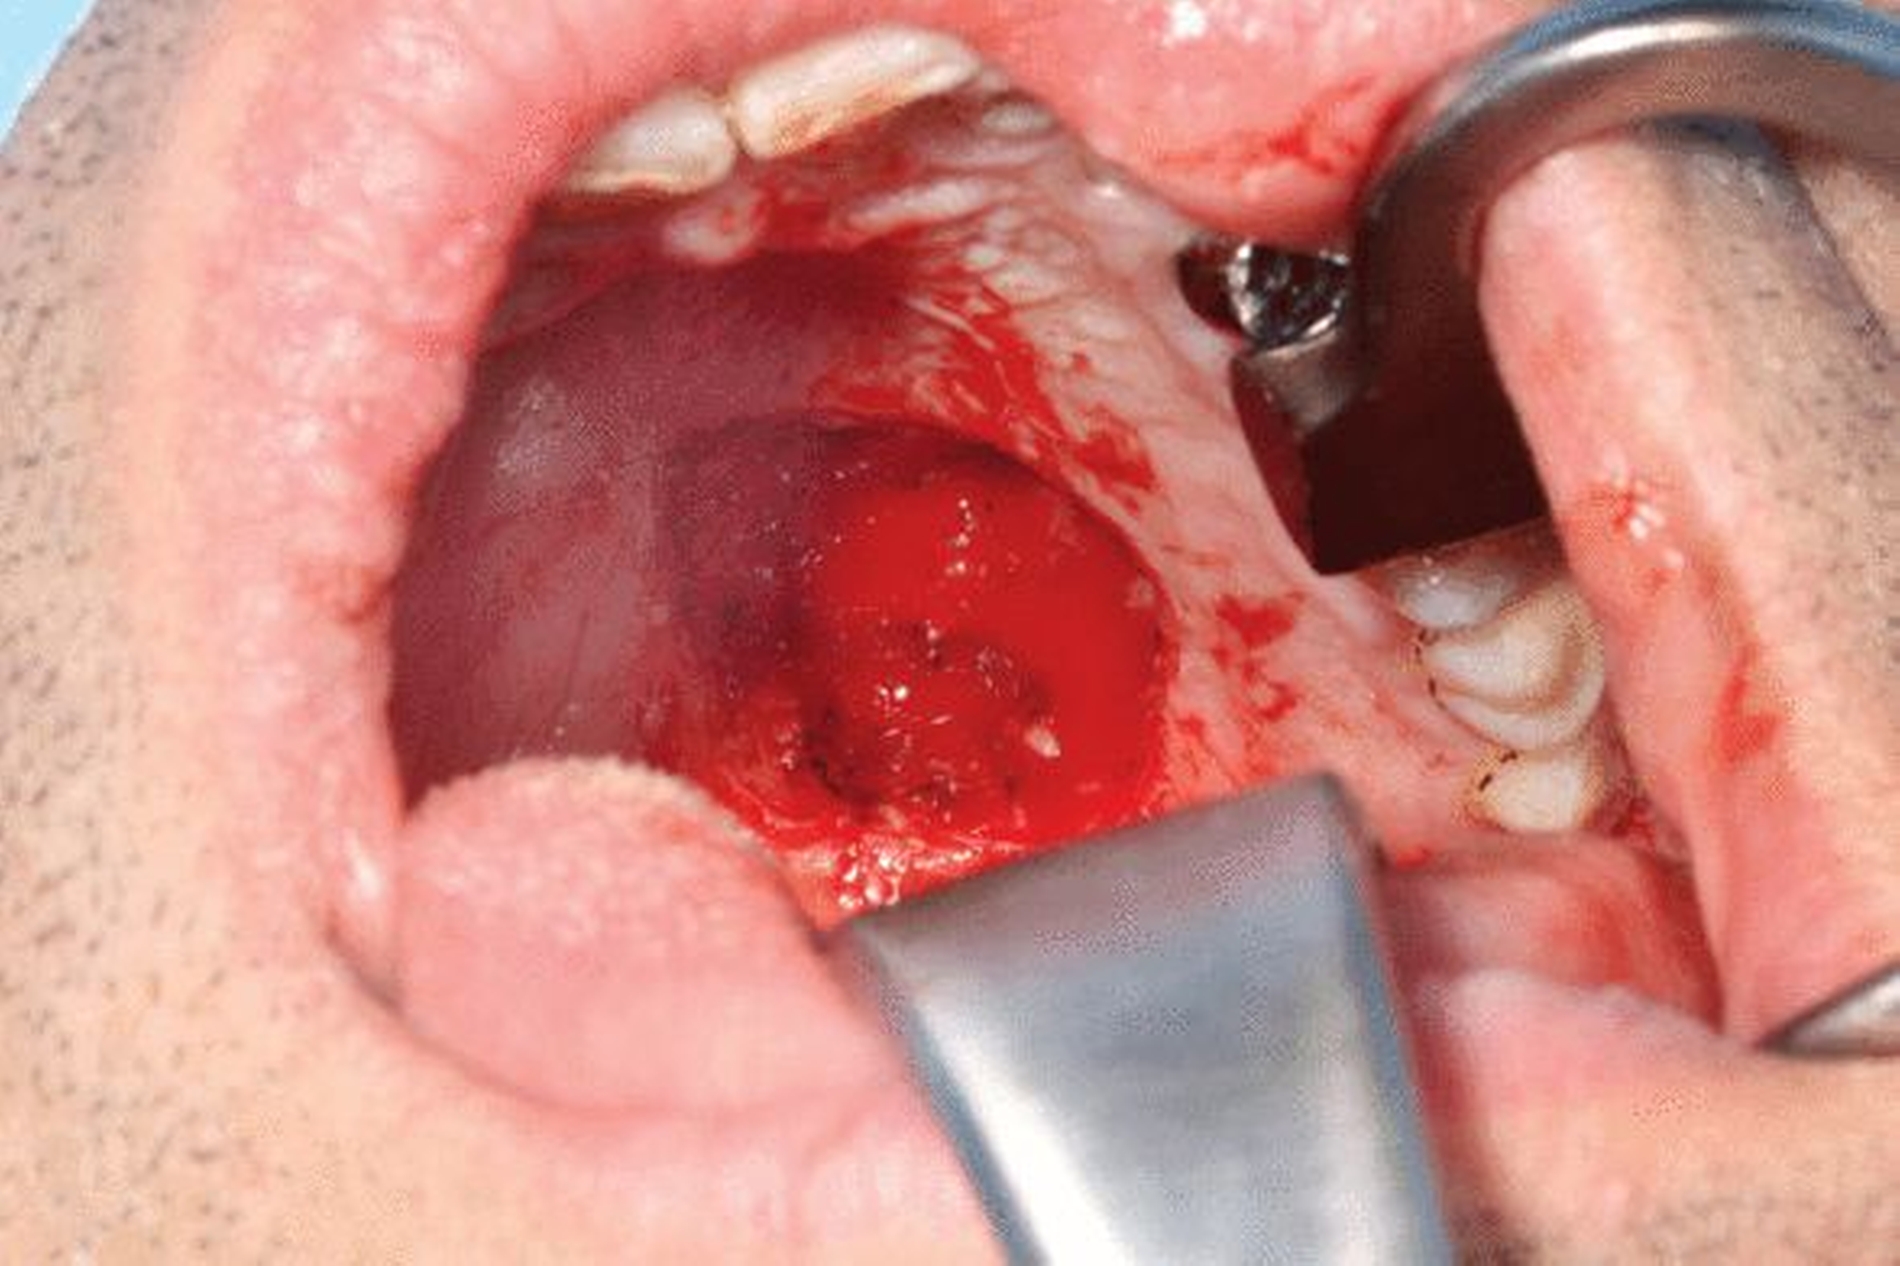

Die geplante Mandibulektomie und sofortige Defektrekonstruktion des Unterkiefers erfolgte mit einem CAD/CAM-geplanten mikrovaskulär anastomosierten Fibulatransplantat aus dem rechten Unterschenkel (Abbildung 3). In der darauf folgenden Operation wurden das Rezidiv unter Einbeziehung des linken Mundbodens sowie der Unterkiefer vom Kieferwinkel links bis zum Kiefergelenk rechts reseziert (Abbildung 4). Histopathologisch wurde eine R0-Resektion bestätigt.